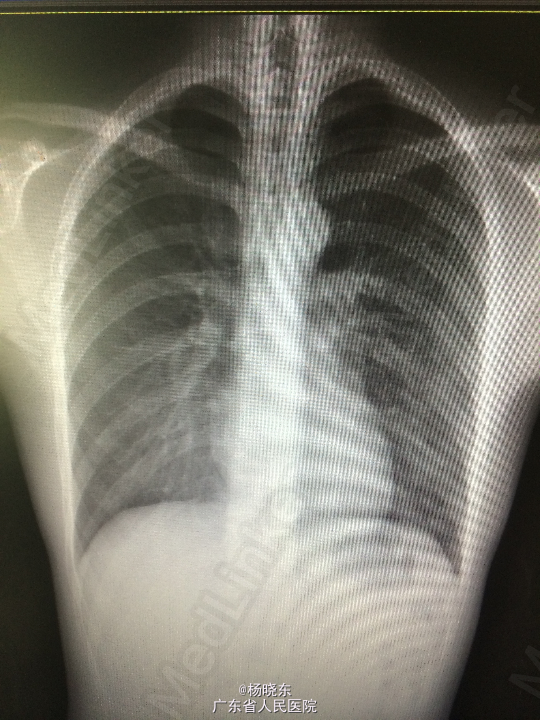

主诉:间断性胸闷、胸痛3年余,再发10余天。 病史:患者于3年余前出现左侧胸闷、胸痛。于当地医院就诊,诊断为左侧气胸(肺压缩10%),予对症处理(具体不详),1年余前再次出现左侧胸痛,于当地医院对症处理后好转,10余天前再次出现左侧胸痛,呈隐痛,无放射性牵涉痛,可忍受。自起病以来,精神睡眠胃纳可,大小便正常,体重无明显变化。

查体:心肺腹查体无特殊。 辅查:胸片

诊断:气胸 处理:完善相关检查后行胸腔镜双侧胸膜固定术,肺大疱切除术